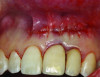

Patient 1: A 30-year-old female patient with an unremarkable medical history presented with implant No. 9 exhibiting retrograde peri-implantitis. Tooth No. 9 had been replaced with the implant 8 years prior because of a history of trauma and failed root canal treatment. The implant exhibited a periapical radiolucency with the sinus tract tracing to the apex of implant No. 9 (Figure 1 and Figure 2). The patient had a high smile line with longer clinical crowns at Nos. 9 and 10 compared with Nos. 7 and 8 (Figure 1 and Figure 2).

Fig 1 and Fig 2. Case 1: Initial clinical presentation with gutta-percha placed in the apical fistula of tooth No. 9 (Fig 1); radiograph showing gutta-percha point leading to the periapical lesion (Fig 2).